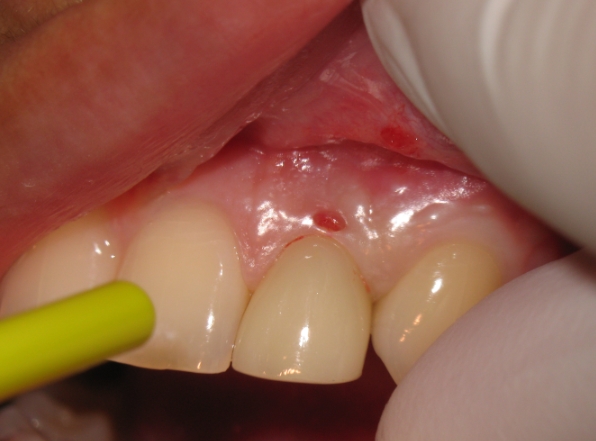

누구라도 치아와 잇몸 경계 사이에는 골이 있습니다. 정상 깊이는 1~2mm 정도인데 3mm이상이 되면 치주포켓이라고 부릅니다. 즉 잇몸고랑이 깊숙하게 패인 것을 말합니다. 이 안에 세균이 증식하면 잇몸이 붓고 출혈을 일으키고 이대로 방치하면 잇몸 염증 고름이 나오게 됩니다.